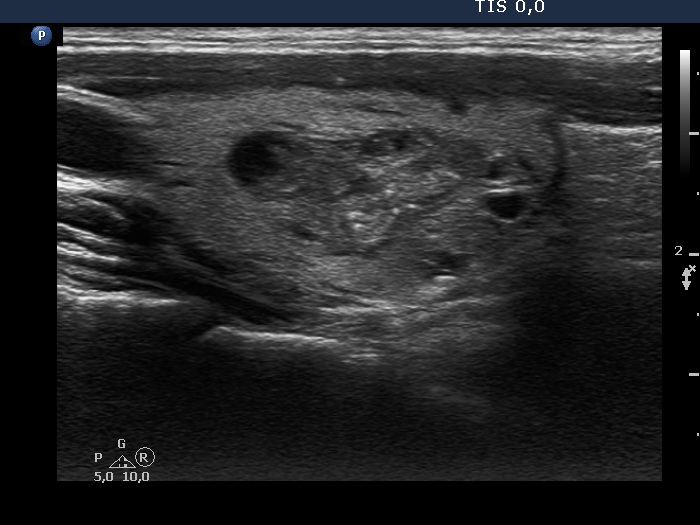

Study on 100 consecutive patients with thyroid nodule - case 030 (ultrasonographic picture 11)

Right lobe, longitudinal scan - after aspirating 6 mL brown fluid. The bright echogenic figures may deceive us if we are not aware that they were present before aspiration.